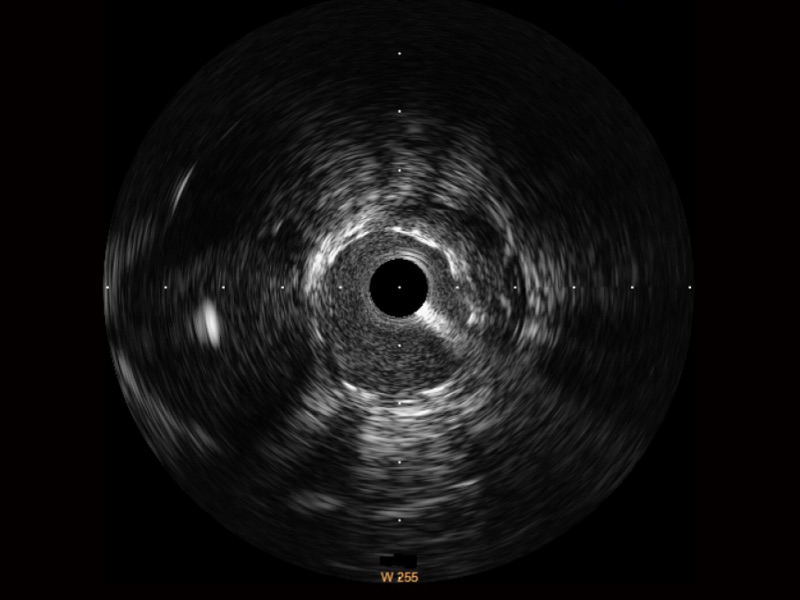

db真人体育官网宽频IVUS图像

对比传统IVUS导管成像,db真人体育官网宽频IVUS图像的近场支架梁显影更细腻,远场中膜外血管仍清晰可辨,兼顾远中近,兼顾分辨力与穿透深度